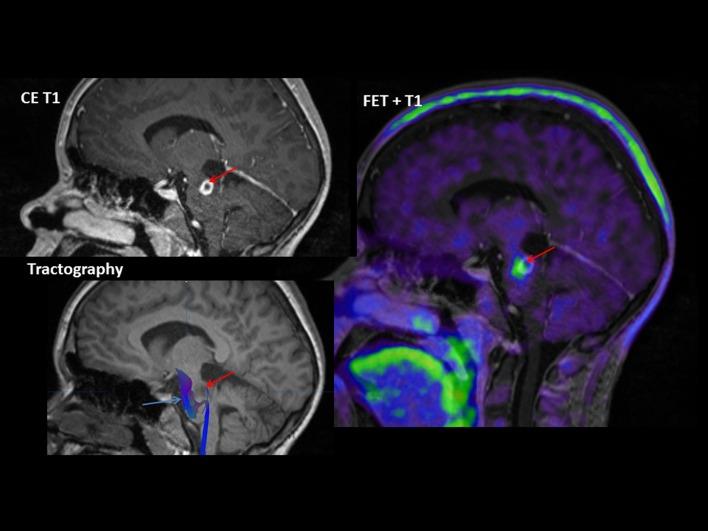

Clinical PET/MRI in neurooncology: opportunities and challenges from a single-institution perspective.

Magnetic resonance imaging (MRI) plays a key role in neurooncology, i.e., for diagnosis, treatment evaluation and detection of recurrence. However, standard MRI cannot always separate malignant tissue from other pathologies or treatment-induced changes. Advanced MRI techniques such as diffusion-weighted imaging, perfusion imaging and spectroscopy show promising results in discriminating malignant from benign lesions. Further, supplemental imaging with amino acid positron emission tomography (PET) has been shown to increase accuracy significantly and is used routinely at an increasing number of sites. Several centers are now implementing hybrid PET/MRI systems allowing for multiparametric imaging, combining conventional MRI with advanced MRI and amino acid PET imaging. Neurooncology is an obvious focus area for PET/MR imaging.

Based on the literature and our experience from more than 300 PET/MRI examinations of brain tumors with F-fluoro-ethyl-tyrosine, the clinical use of PET/MRI in adult and pediatric neurooncology is critically reviewed.

磁共振成像(MRI)在神经肿瘤学中发挥着关键作用,即用于诊断、治疗评估和复发检测。然而,标准MRI并不总能将恶性组织与其他病变或治疗引起的变化区分开来。诸如扩散加权成像、灌注成像和波谱学等先进的MRI技术在鉴别恶性与良性病变方面显示出有前景的结果。此外,氨基酸正电子发射断层扫描(PET)补充成像已被证明能显著提高准确性,并且在越来越多的机构中被常规使用。现在有几个中心正在安装PET/MRI混合系统,以实现多参数成像,将传统MRI与先进MRI及氨基酸PET成像相结合。神经肿瘤学显然是PET/MR成像的一个重点领域。

基于文献以及我们对300多例使用F-氟代乙基酪氨酸进行脑肿瘤PET/MRI检查的经验,对PET/MRI在成人和儿童神经肿瘤学中的临床应用进行了批判性综述。